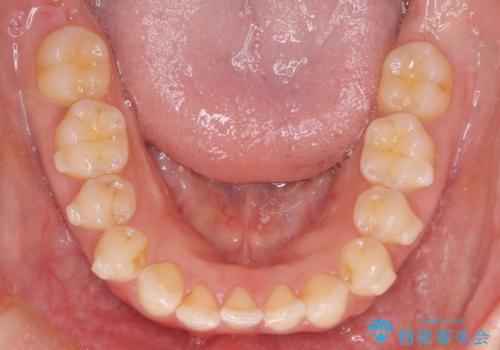

- 下顎前歯の叢生を主訴に来院されました。

臼歯関係の状態から下顎前歯一本の抜歯を行う治療計画を立て、インビザラインを使用して治療を行いました。

今回の抜歯ケースはインビザラインでも綺麗に治ります。